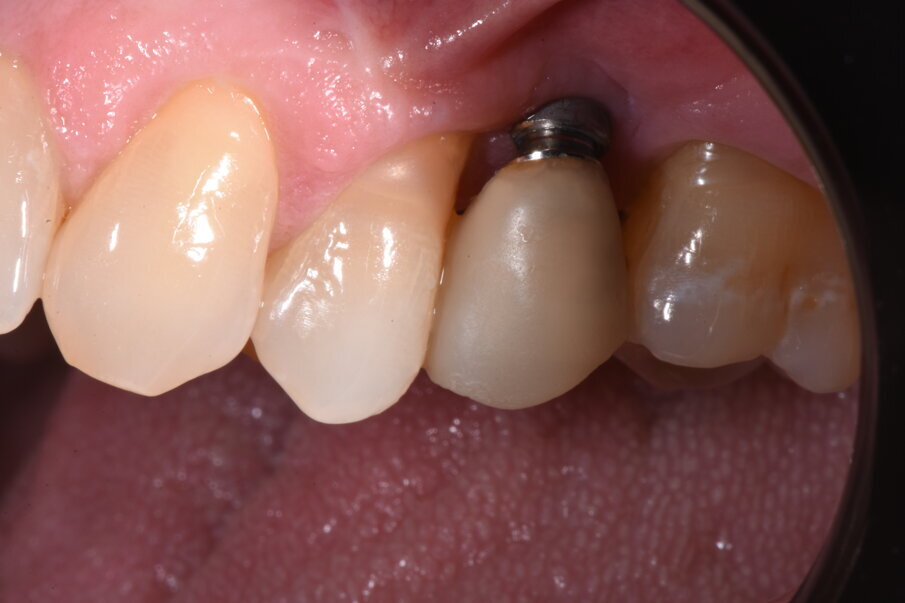

La paziente si presenta all’attenzione dello studio riferendo fastidi nella zona superiore sx, e all’anamnesi risultano trascorsi 3 anni dall’ultimo appuntamento di igiene presso altro centro. L’esame visivo e fotografico (Fig. 1) evidenziano un’alterazione dello stato dei tessuti perimplantari con sanguinamento spontaneo e lassità del tessuto molle, pertanto segue acquisizione di rx endorale da parte dell’odontoiatra (Fig. 2) da cui risulta un’importante riassorbimento osseo a carico dell’impianto. Segue un sondaggio perimplantare profondo (Fig 3), eseguito previa anestesia topica con Lidocaina 15%, per definire estensione e conformazione del difetto associandolo alla valutazione radiografica per la conta delle spire esposte.

Fig. 1